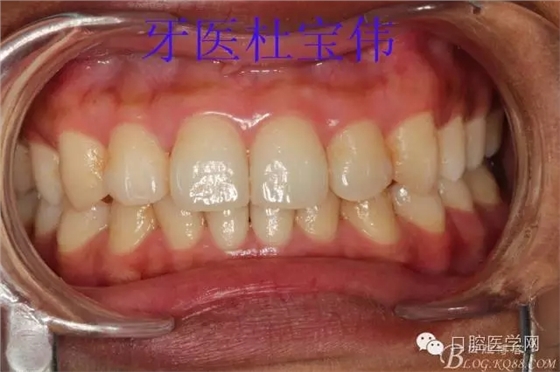

患者都是以刷牙出血為主訴。術(shù)前照片

術(shù)后照片